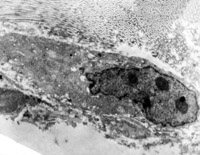

5-2-8 伤后第10天,皮肤附件上皮细胞成簇散布,核仁边集,内质网扩张,胞质内含较多张力原纤维  TEM×6000